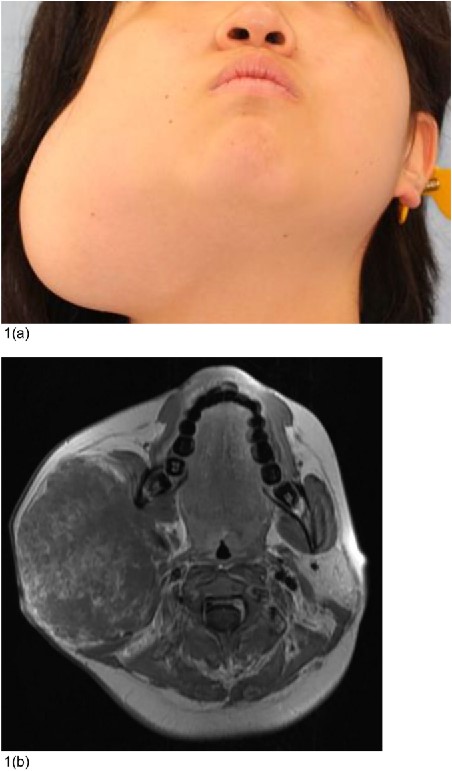

Examination revealed a 10 cm × 6 cm subcutaneous mass in the right parotid area (Fig. 1a), causing facial contour asymmetry. Notably, there was no facial nerve paralysis.

Preoperative condition. (a) A 16-year-old woman had a subcutaneous mass measuring 10 × 6 cm in the right parotid area. Her facial contours were asymmetrical. (b) MRI images displayed a 75 mm × 97 mm × 87 mm lobulated mass with heterogeneous internal contrast.

Magnetic resonance imaging (MRI) displayed a 75 mm × 97 mm × 87 mm lobulated mass with heterogeneous internal contrast, indicating a low-flow VM.